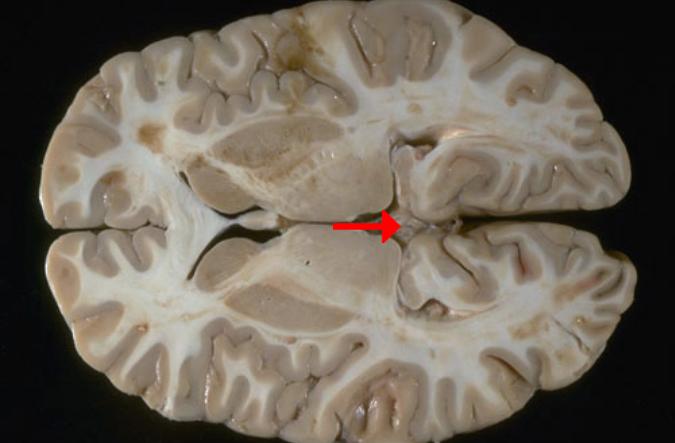

Label this brain part

Fornix

Label this brain structure

Caudate nucleus

Label this brain structure

Putamen

Label this brain structure

Globus pallidus

Label this brain structure

Amygdala

Label this brain structure

Septum pellucidum